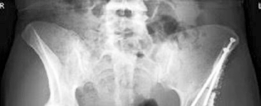

Standard radiographic evaluation includes an anteroposterior pelvis radiograph, a false profile view of Lequesne, and a Dunn lateral or cross-table lateral view. The AP pelvis allows for the measurement of the LCE angle, Tönnis angle, extrusion index, and evaluation of the Shenton line. The false profile view is critical for assessing anterior femoral head coverage (ACE angle) and evaluating the anterior joint space.

Advanced imaging with computed tomography (CT) with 3D reconstruction is increasingly utilized. 3D CT allows for precise mapping of the bony anatomy, evaluation of acetabular version, and virtual surgical planning. Magnetic resonance imaging (MRI) or MR arthrography is routinely obtained to evaluate the integrity of the labrum, articular cartilage, and ligamentum teres. Concomitant intra-articular pathology is highly prevalent in dysplastic hips and must be factored into the surgical plan, often necessitating a combined approach with hip arthroscopy or open arthrotomy.

Once the osteotomies are complete, a Schanz pin is inserted into the supra-acetabular region of the mobilized fragment. The fragment is manipulated using a combination of flexion, internal rotation, and medialization to achieve optimal coverage. The goal is to achieve an LCE angle of 25 to 30 degrees, a neutral Tönnis angle, and slight anteversion of the acetabulum, while medializing the hip center.

Provisional fixation is achieved with Kirschner wires. The hip is then taken through a full range of motion to ensure there is no anterior impingement (which can occur if the fragment is over-rotated anteriorly) and that joint congruity is optimized. Fluoroscopy confirms the correction. Definitive fixation is typically achieved with three or four 3.5mm or 4.5mm fully threaded cortical screws directed from the stable ilium into the reoriented acetabular fragment.